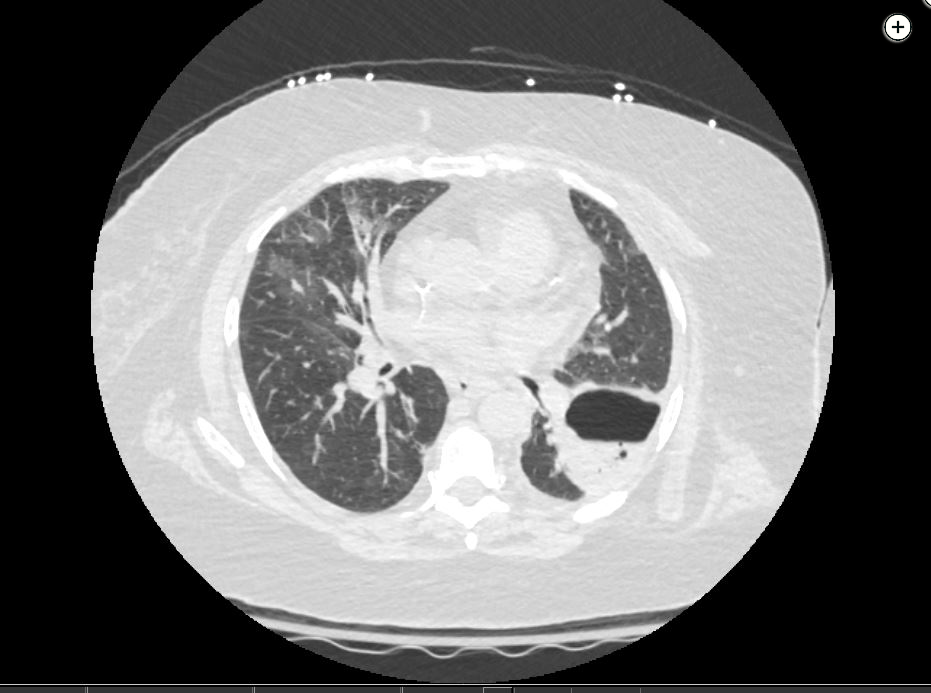

Pulmonary abscess is a collection of pus within the lung parenchyma with confined cavitation that results from a pulmonary infection.

- risk of rupture into the airway or pleural space